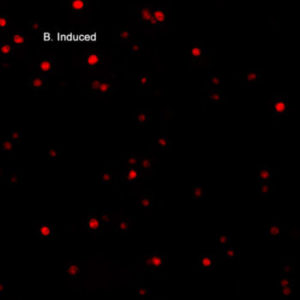

(Jurkat cells were treated with 1 uM staurosporine toinduce caspase 9 activity (left), or a negative control(right) for 3 hours, washed twice, then incubated withICT's red caspase 9 inhibitor probe, SR-LEHD-FMK, for 1hour and examined under a fluorescence microscope.DIC images were also taken of all cells. Both inducedimages reveal several experimental cells which fluorescered, therefore they have some degree of caspase 9activity. The non-induced DIC image reveals many controlcells, however the corresponding fluorescence image isdark; none of these cells have active caspase 9 (Dr. BrianW. Lee, ICT).)